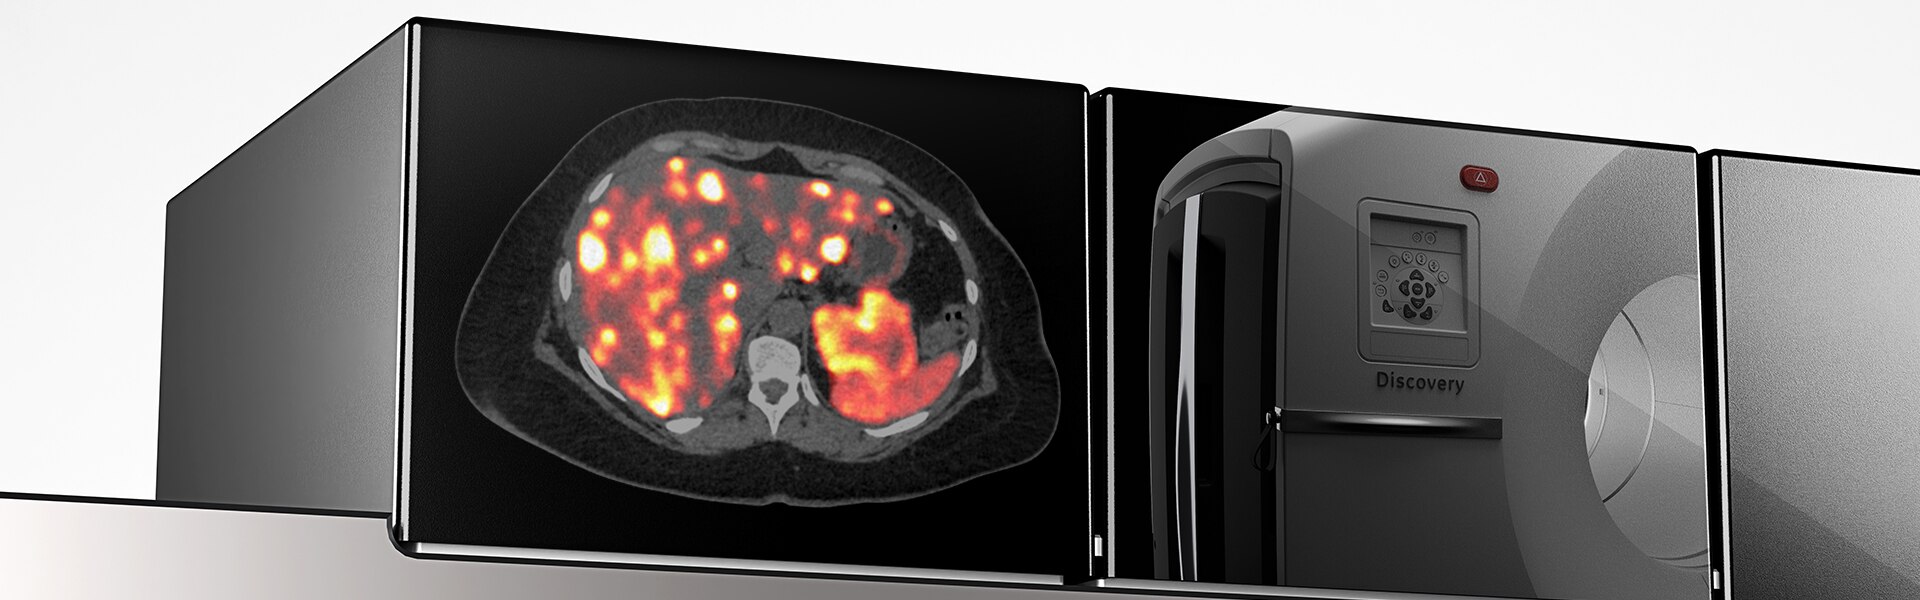

Discovery MI Gen 2 Overview

Detección digital remasterizada

El Discovery MI Gen 2 está hecho para ofrecer

- Un campo de visión escalable

- Un aumento del 50% en el pico de NECR4

- Sensibilidad excepcional por cm (cps/kBq/cm)

- Una reducción del 33% en el tiempo de escaneo4

- Una reducción del 33% en la dosis inyectada4

Una nueva generación de PET digital